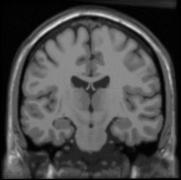

We extended a previously demonstrated entropy based groupwise registration method to include a free-form deformation model based on B-splines.

The objective in groupwise registration is to bring subjects in a population into joint alignment in order to establish correspondences among anatomical structures.